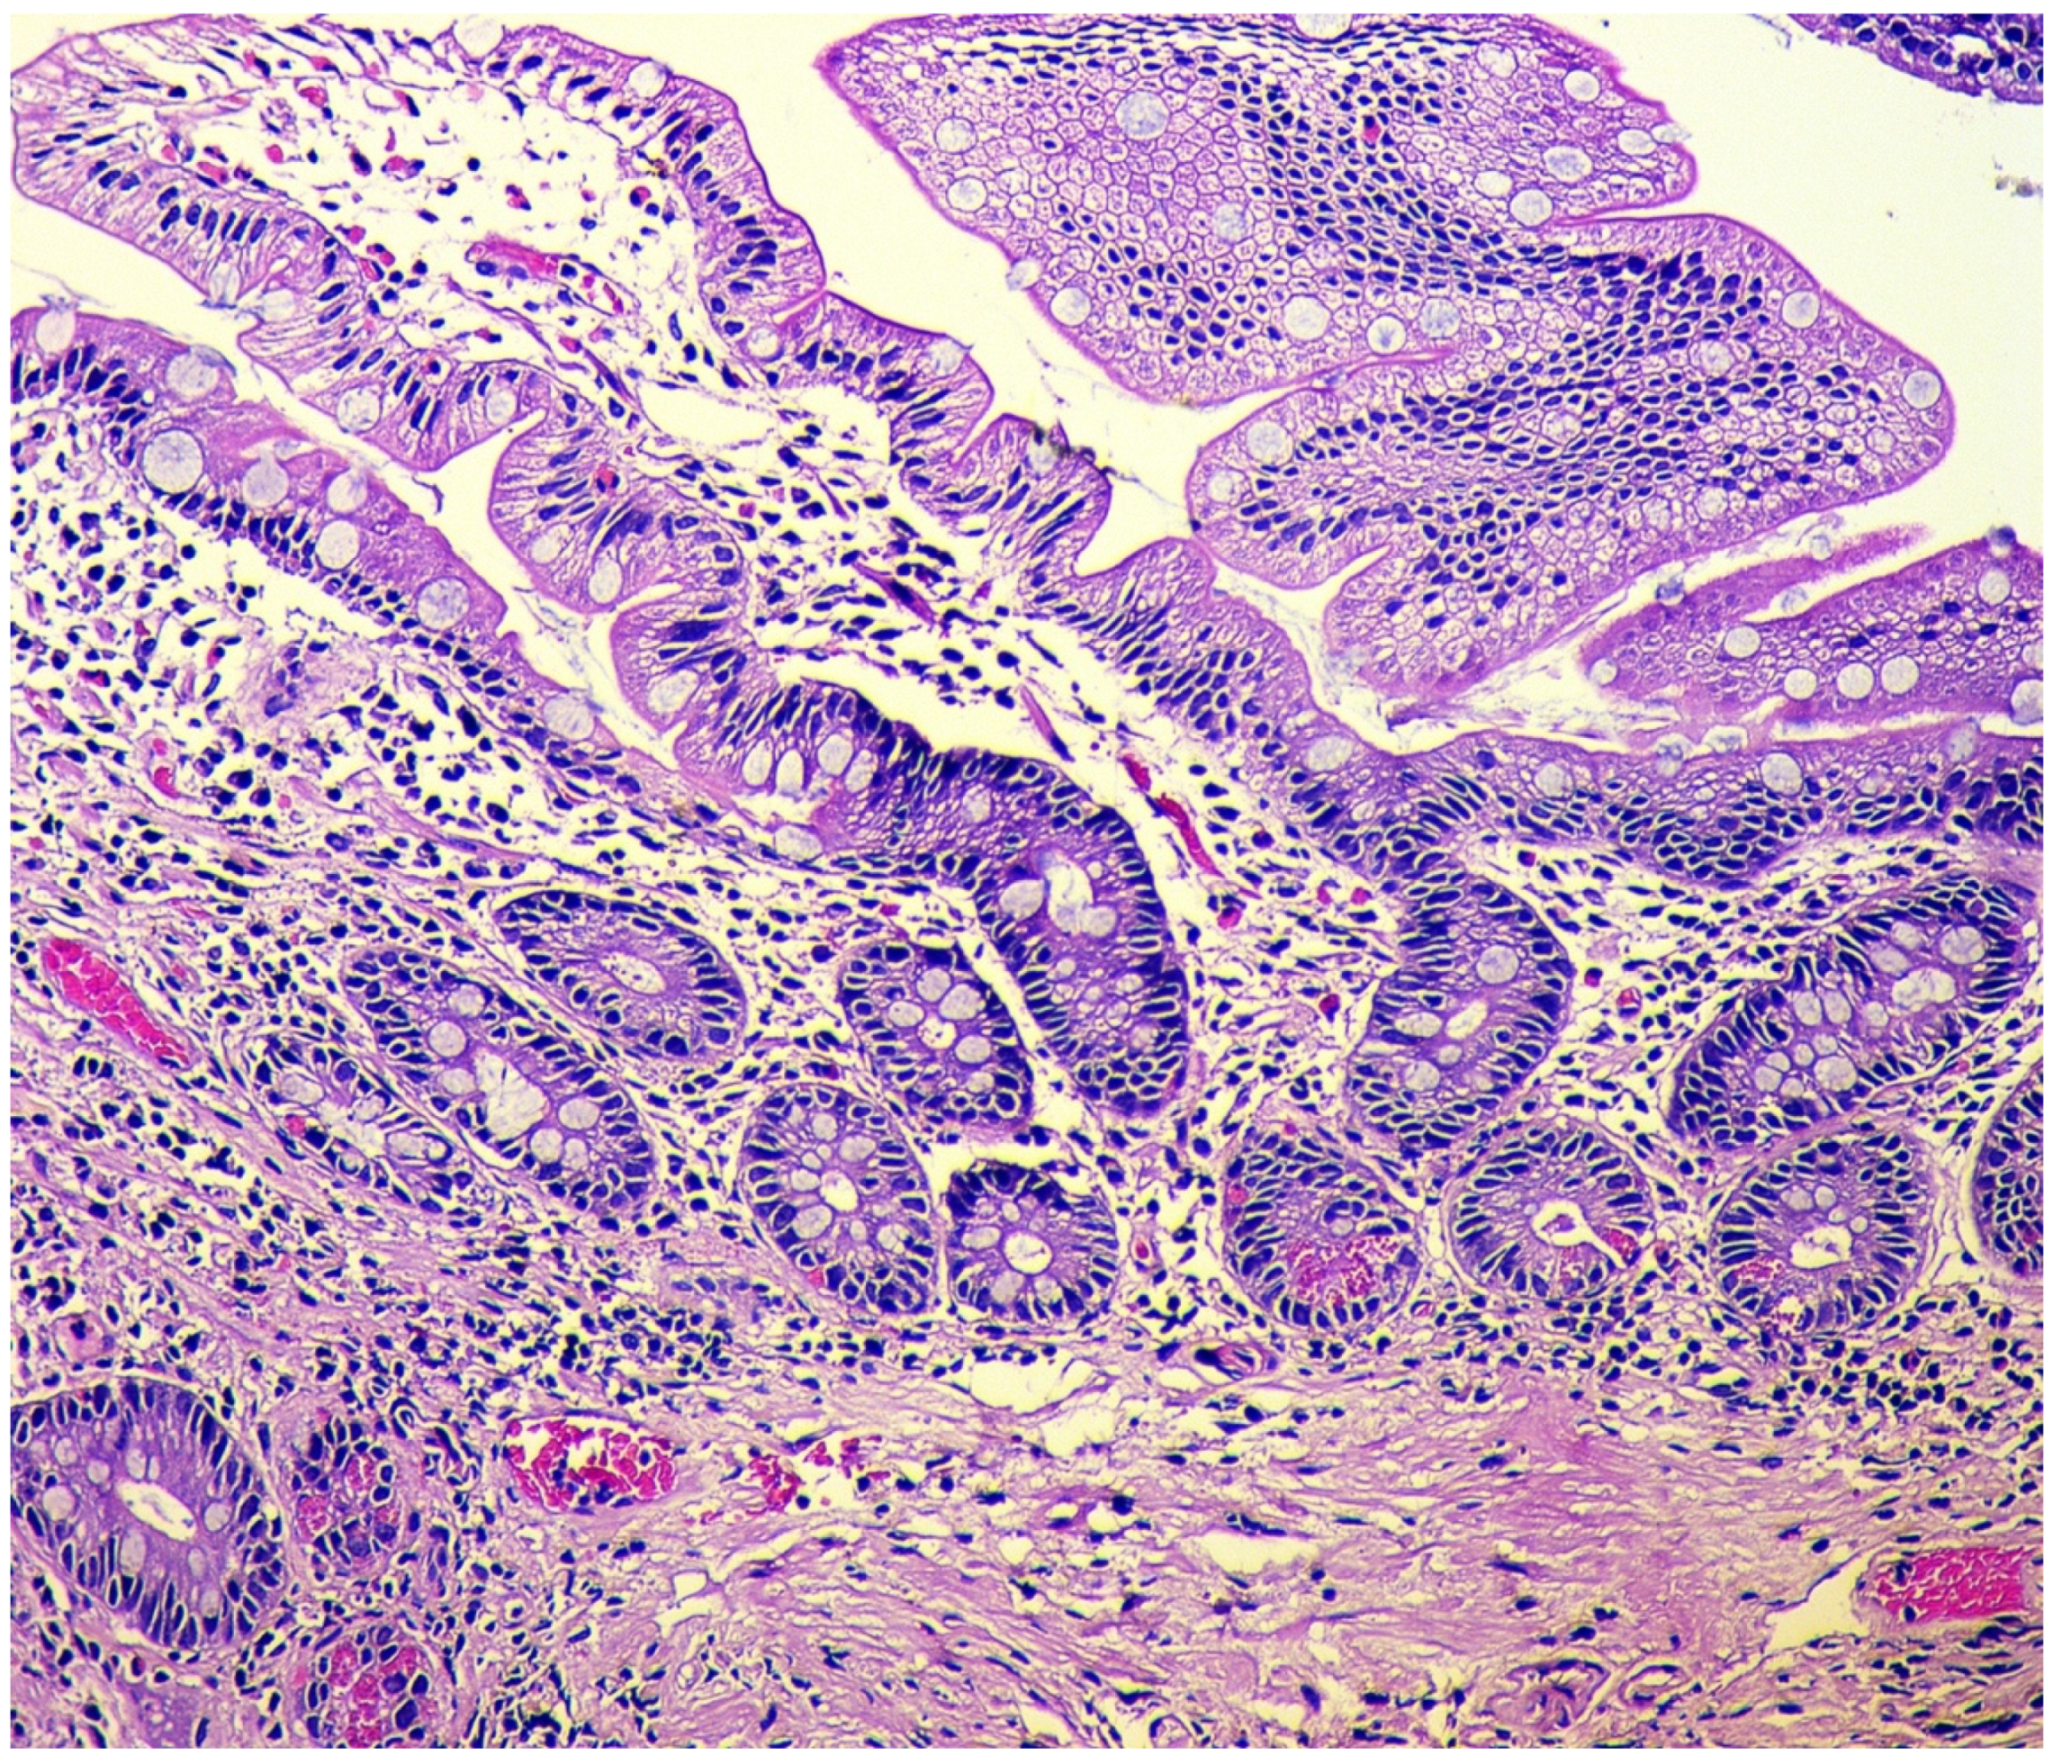

- Simple diffuse hyperplasia. This is characterized by a more than two-fold increase in the population of ECL cells. Diagnosis is difficult due to the lack of clear quantitative criteria. The diagnosis is poorly reproduced on biopsy material.

- Linear hyperplasia. The presence in one visual field of at least two groups of linearly located neuroendocrine cells, consisting of five or more cells. Usually, changes are diagnosed in the area of the neck glands (Figure 4).

- Micronodular hyperplasia. The presence of the cells’ cluster in contact with the basement membrane, but not exceeding the diameter of the gland, up to 150 μm in diameter, or a similar cluster located freely in the lamina propria of the mucous membrane.

- Adenomatous (adenomatoid) hyperplasia. The presence of an aggregate of five or more clusters (Figure 5).

- Neuroendocrine cells dysplasia. Merging clusters with diameters of more than 150 µm but less than 500 µm.